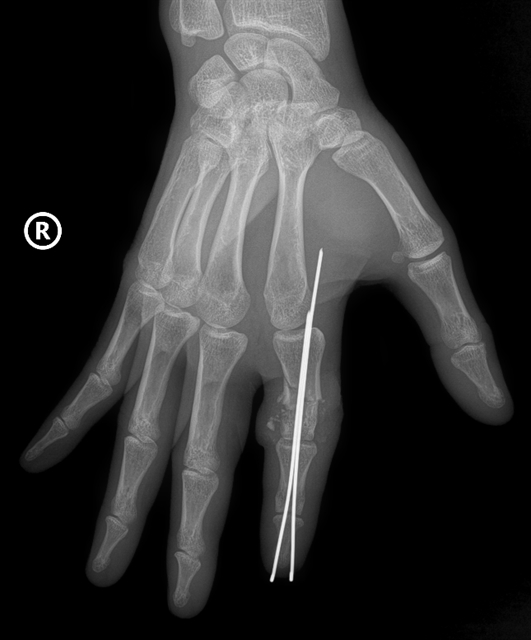

An X-ray image shows the patient’s severed finger after it was aligned and fixed with specialised pins.

Two surgical teams worked simultaneously, with one preparing the detached finger and the other the stump. Surgeons stabilised the bone with specialised pins, repaired tendons and ligaments and reconnected nerves and blood vessels less than one millimetre in diameter using high-powered microscopes.